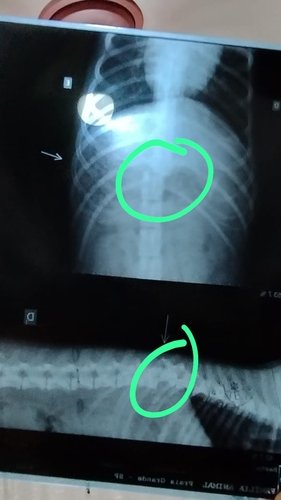

Após exames radiográficos, foi constatado que o Bartô está com uma fratura de coluna muito grave e precisará realizar uma cirurgia para colocação de pinos e hastes.

**Fotos de antes da cirurgia**